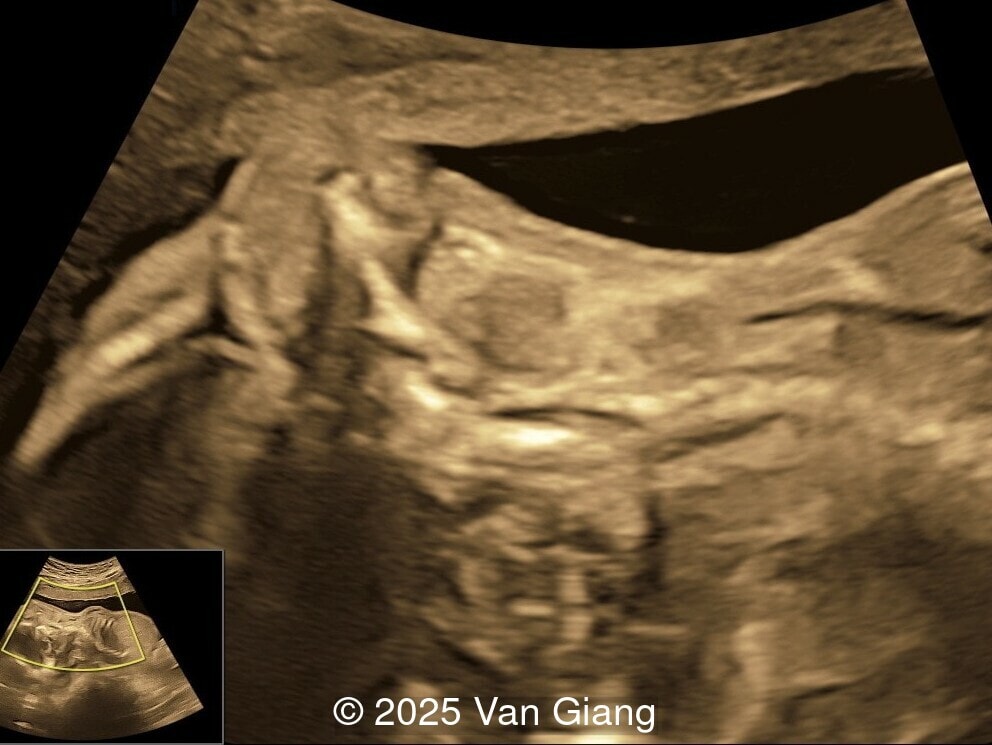

A 32-year-old primigravida presents at 20 weeks gestation without first trimester screening. Ultrasound reveals a small for gestational age fetus with the following anomalies:

We present a case of Nager syndrome.

Ultrasound revealed severe mandibular and zygomatic hypoplasia, glossoptosis, cleft palate, and micrognathia with an abnormal facial profile. Both upper limbs showed radial ray sequence with abnormal thumbs and shortened forearms. Unilateral clubfoot was also noted. No major cardiac or visceral anomalies were observed. Based on these findings, Nager syndrome was suspected.

Unilateral clubfoot

Image 5 Unilateral clubfoot